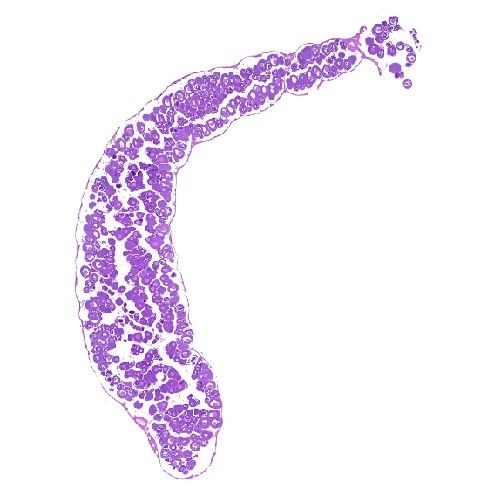

病理平臺可承接:石蠟切片,切片掃描,熒光掃描,HE染色,各種特殊染色,如:Masson、油紅O、PAS、番紅O、ALP、TRAP、甲苯胺藍以及免疫組化/熒光、原位雜交等,3D HISTECH滿足對結果高質量,高標準,周期快的實驗外包需求,并提供染色培訓服務,分線上視頻,線下實操帶教兩種培訓方案。